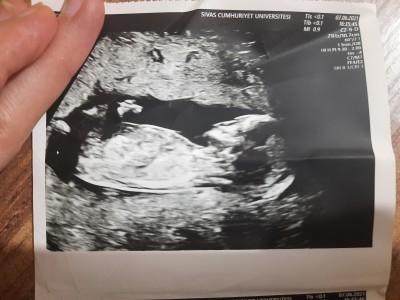

Ultrasona göre cinsiyet tahmini yapabilecek varmı resimli13+3

Cinsiyet tahmini anlayan varmı

Erkek gibimsi bacim dr bisey demedimi

Canim doktor gördü sanki ama gülerek birdahaki gelmene dedi söyleyeyim bilerek sanki demedi bir daha da insalllah 1 aya gidicem merak ettim baya

Sadece sallıyorum canm içimden geçen erkek bebek :) sağlıklı olsun da Allah gönlüne göre versin

Bence kızın olacak :)